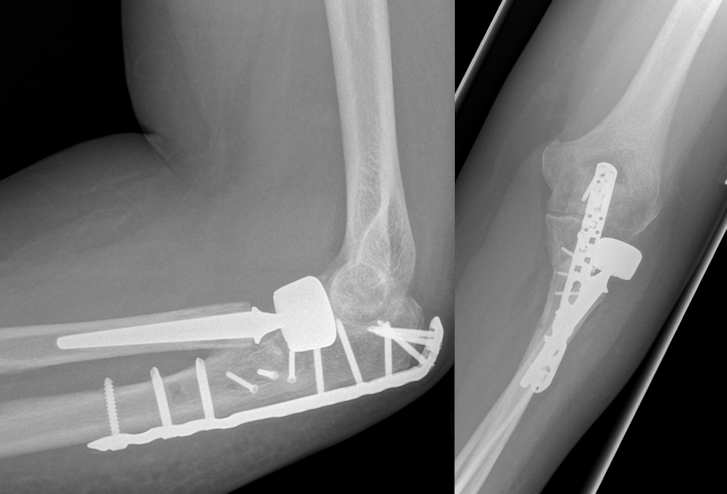

Osteosynthesis of the ulna was performed using a proximally contoured 3.5 mm LCP (locking compression plate) or precontoured 3.5 mm LCP Olecranon Plate (both Synthes GmbH, Umkirch, Germany) applied to the posterior surface of the ulna in dynamic compression mode (Figure 1 [Fig. 1], Figure 2 [Fig. 2], Figure 3 [Fig. 3]).

Figure 2: Postoperative radiographs. Osteosynthesis of the ulna was performed using a proximally precontoured olecranon plate applied to the posterior surface of the ulna. Implantation of a cemented bipolar radial head prosthesis.

Figure 3: Same patient 11 months after the injury: no degenerative changes and heterotopic ossifications. No signs of loosening of the radial head prosthesis. Good clinical outcome.